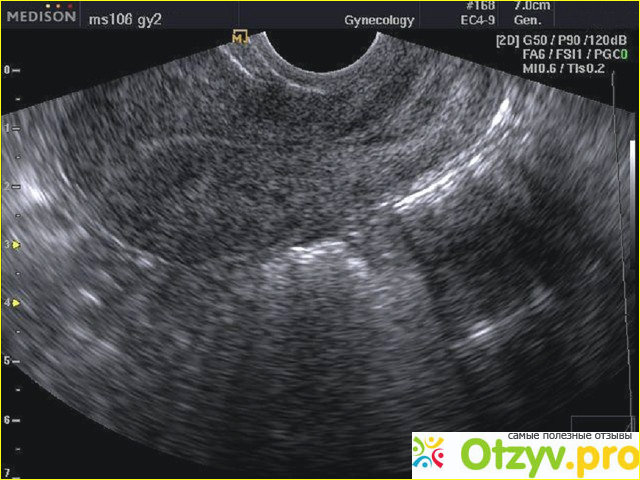

Узи часто применяется при диагностике заболеваний желудочно-кишечного тракта, при диагностике многих заболеваний в области гинекологии, заболеваний опорно-двигательного аппарата. Особенно актуально проведение ультразвукового исследования при беременности, чтобы увидеть в каком состоянии находится плод, определить его пол. Многих очень интересует вопрос, а с какого возраста возможно проведение данной процедуры и насколько она безопасна?